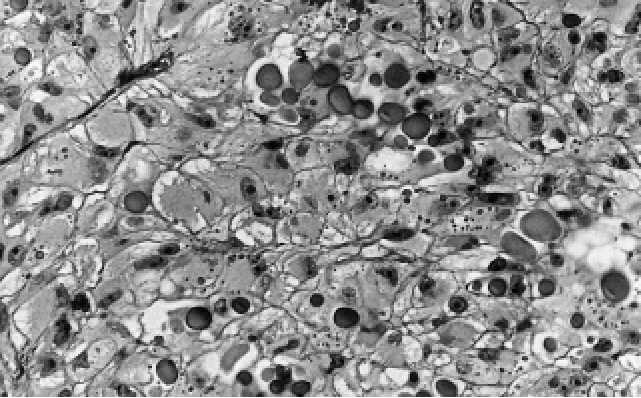

poruje jednotu granulárního a světlobuněčného renálního karcinomu(16). Granulární

změny v cytoplazmě renálního karcinomu mohou postihovat buďto celý tumor

(Obr. B.2.5.) nebo jedna část karcinomu může vypadat jako světlobuněčný kon-

venční renální karcinom a druhá část jako granulární karcinom (Obr. B.2.6.) Tyto dvě

Obr. B.2.6. Část konvenčního karcinomu vypadá jako světlobuněčný renální a část jako gra-

nulární konvenční renální karcinom.